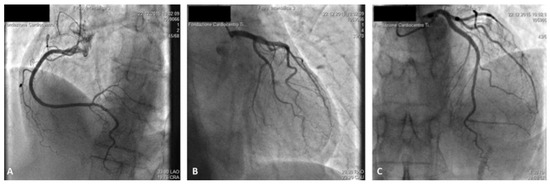

Pacemaker implantation via the femoral vein has been described since the 1980s. This technique is not very well known, but may be useful in some circumstances. We describe a case of a patient with sinus dysfunction without superior venous access, in...